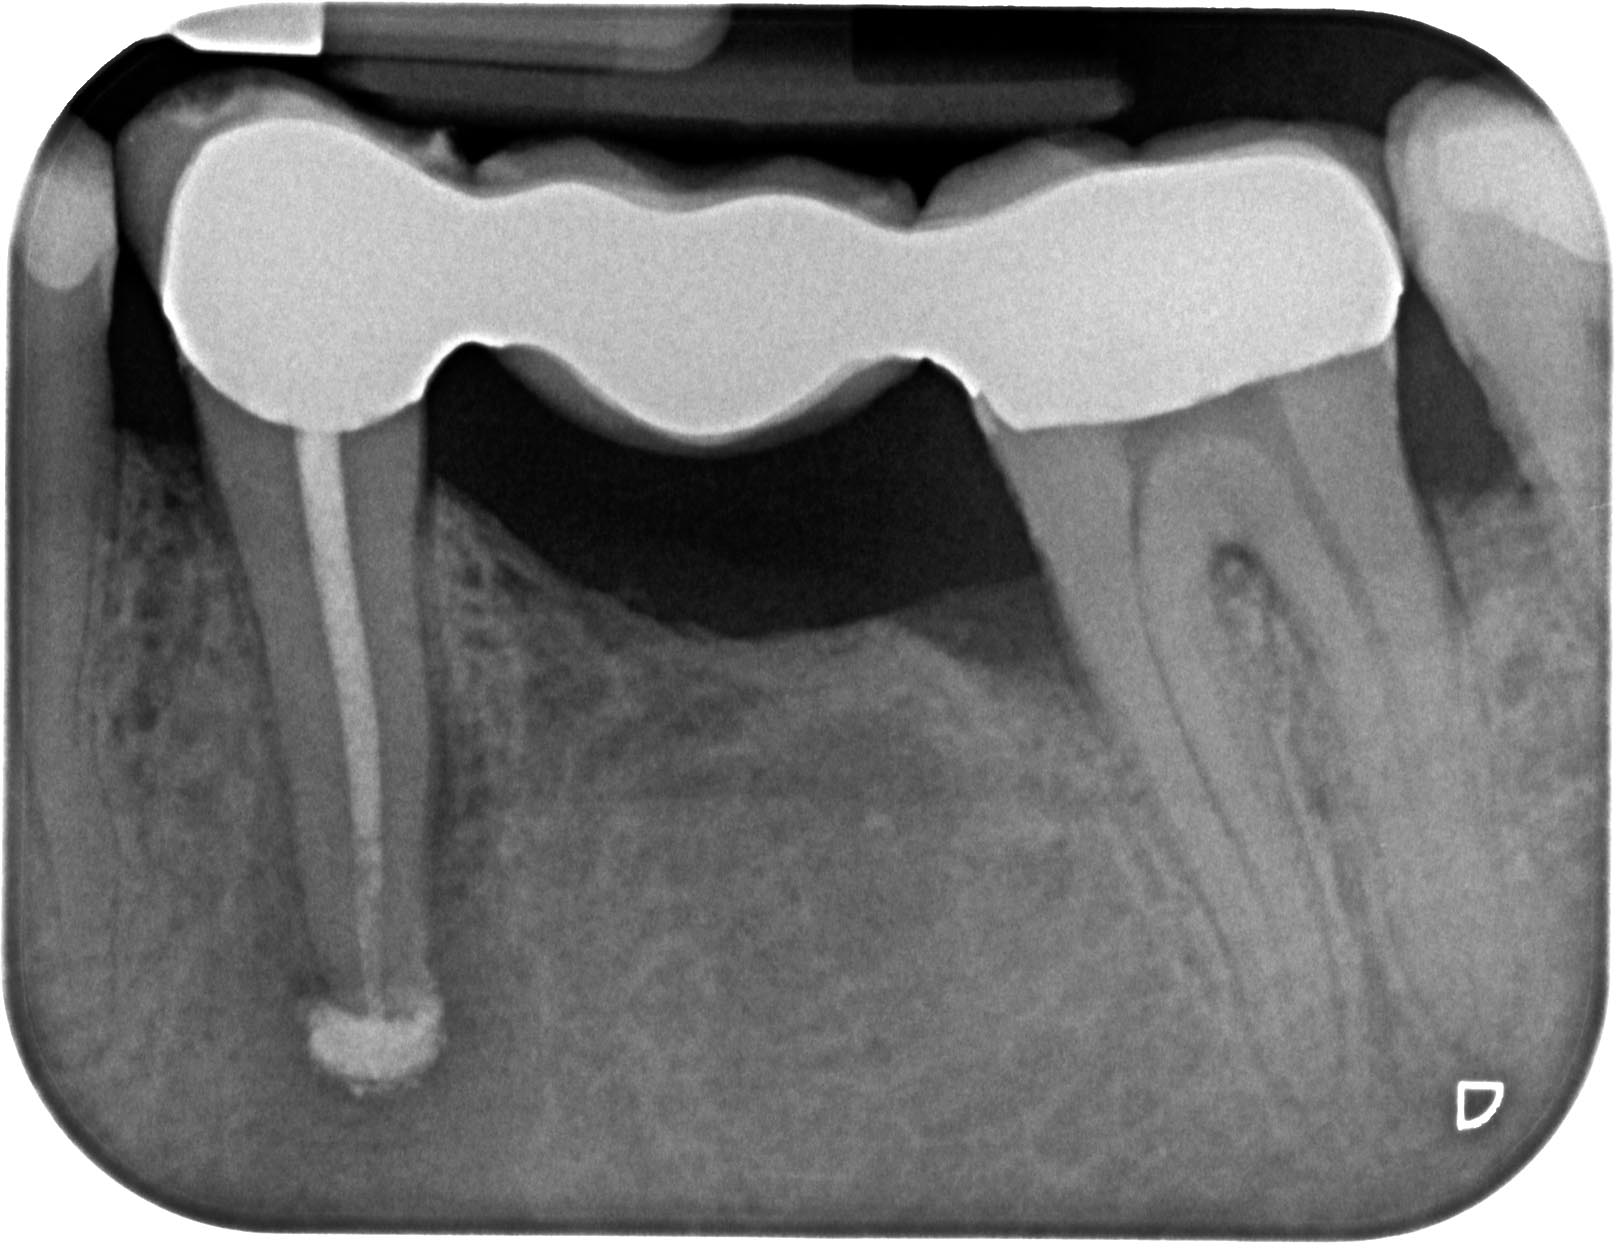

35 Calciumhydroxid apikal überpresst Veröffentlicht 5. November 2013 am 1617 × 1249 in „Chapeau“ oder der Wirt und die Wette 35 Calciumhydroxid apikal überpresst